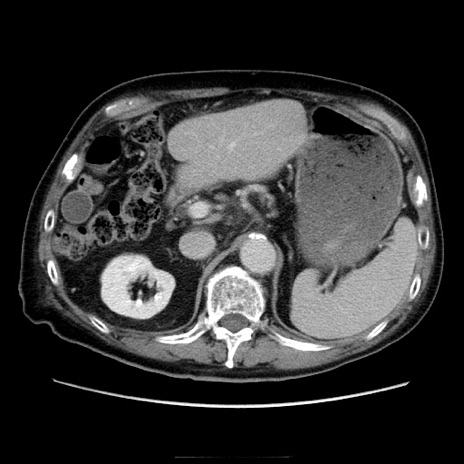

冠状断像

症例21(横断像)

【症例】70歳代男性

【主訴】腹痛

【現病歴】肝硬変・肝細胞癌にてかかりつけの方。約9時間前に食後より腹痛出現。症状が徐々に増悪し、嘔吐出現したため来院。

【既往歴】肝硬変、肝細胞癌(RFA、TACE後)

【身体所見】意識清明、表情苦悶様、BT 36℃、BP 129/78mmHg、P 88bpm、SpO2 97%(RA)、右上腹部から心窩部にかけて圧痛あり、反跳痛なし、筋性防御あり。

【データ】WBC 5800、CRP 0.16